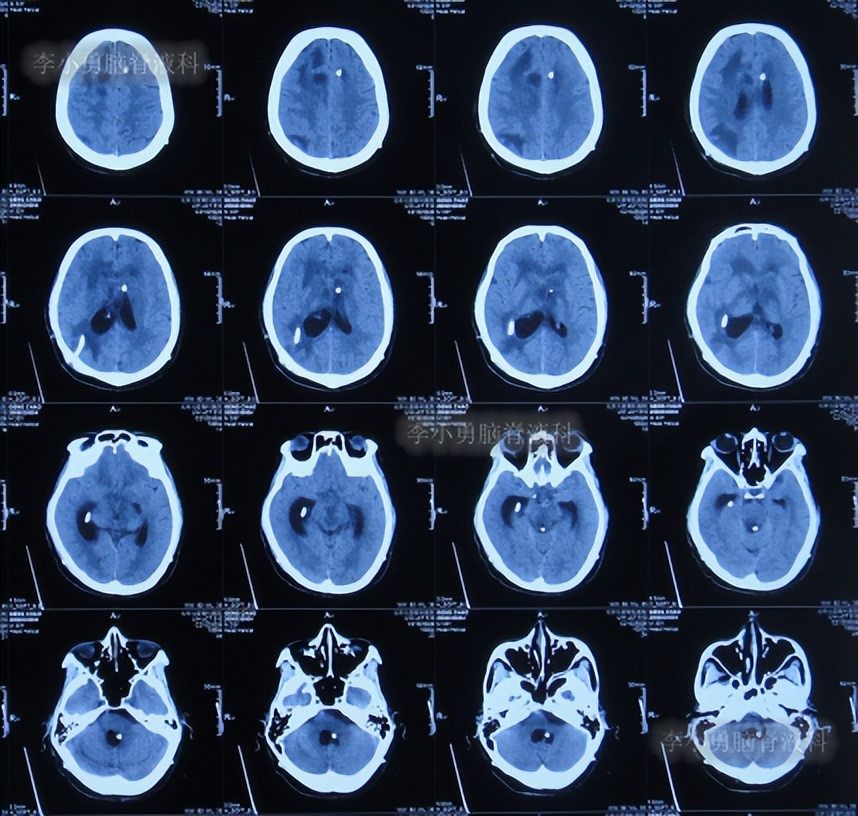

出院后1年半期间,仍时有视物重影的症状,并未给予处理,但到2019年9月27日(脑室腹腔分流术后1年零6个半月),出现头晕,恶心呕吐,视物重影加重,5天后因症状无缓解,就诊于当地的河南省临颍县某医院,查脑CT示脑积水(图-1);给予腰穿检查示颅内压力高220mmH2O。

图-1:2019年10月3日头颅CT